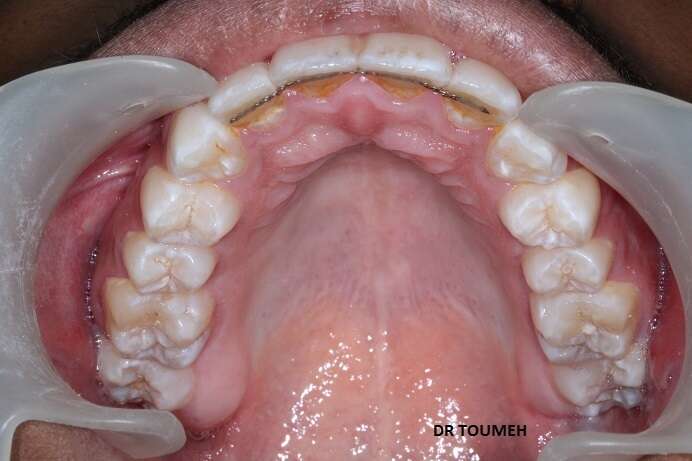

Avant

Après